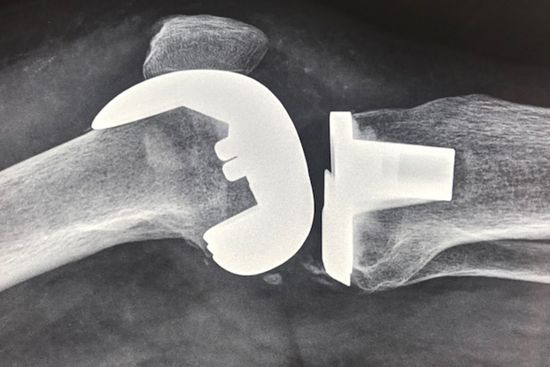

Il dott. Pera si avvale dell'uso di una strumentazione altamente tecnologica per l'elaborazione di diagnosi accurate sulle tutte le patologie ortopediche. In seguito alla corretta individuazione del problema che affligge il paziente, il dottore valuta il tipo di iter da dover seguire per risolvere il disturbo. Il ricorso alle operazioni chirurgiche è necessario solo al manifestarsi di talune patologie e in particolare per:

✔ artroprotesi di ginocchio e anca

✔ chirurgia protesica di ginocchio ed anca